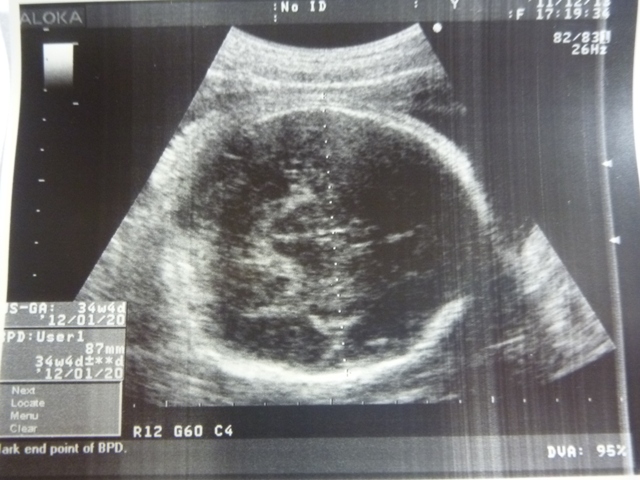

這是測量小貝果的頭圍~腦部也正常~

今天小貝果體重:估約2193~2292g

是週數的正常大小~